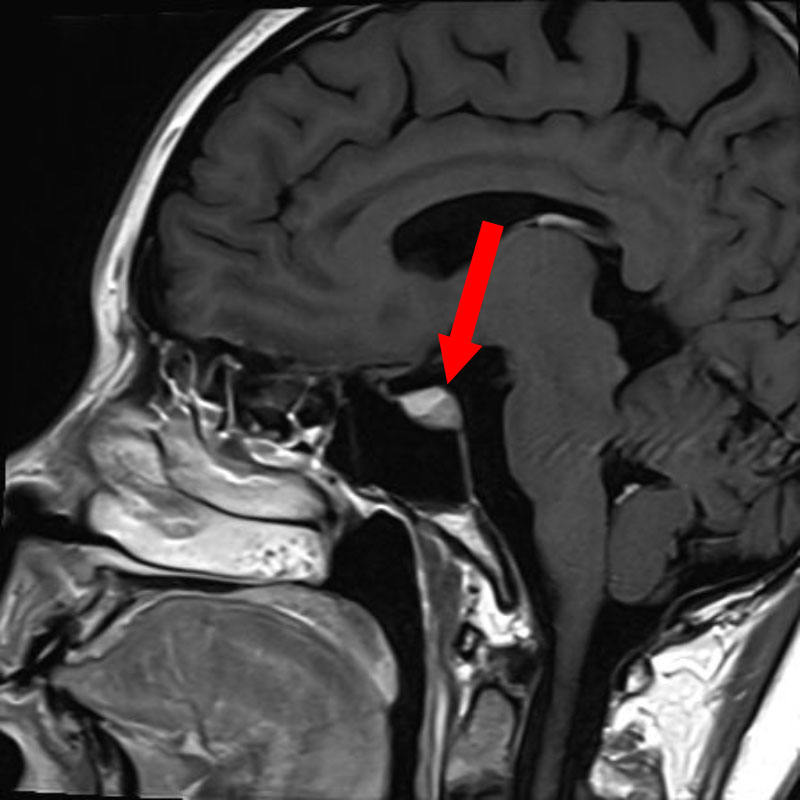

No.’25_103 手術前2